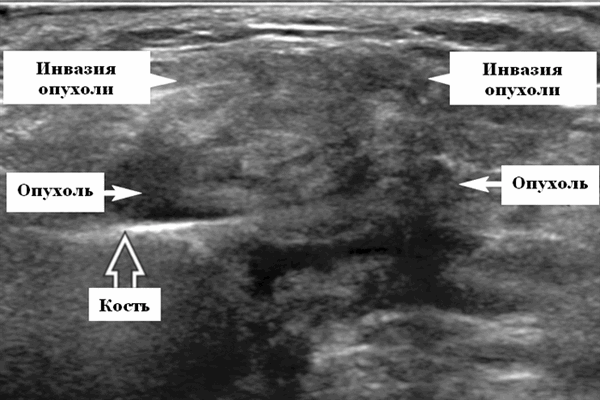

- Необходимо искать локальную инвазию: интрапаротидную, в наружную сонную артерию, ретромандибулярную вену, экстрапаротидные мягкие ткани.

Серошкальное УЗИ. Одиночные или множественные гипоэхогенные образования в известном распределении внутрипаротидных лимфоузлов. Хорошо выраженный или слабо окаймленный (экстранодальное распространение). Экстранодальное распространение. Обратите внимание на местную инвазию интрапаротидной наружной сонной артерии (ВСА), ретромандибулярной вены или экстрапаротидных мягких тканей. Аномальная внутренняя архитектура ± эхогенные ворота. Однородный или неоднородный вид с внутренними кистозными участками в некротических узлах ± метастазы в шейные лимфатические узлы

Серошкальное УЗИ не позволяет отличить АКК от других злокачественных новообразований слюнных желез. Опухоли низкой степени злокачественности могут быть хорошо определены с однородной внутренней архитектурой. Опухоли высокой степени злокачественности плохо определены с инвазивными краями и неоднородными участками некроза / кровоизлияния ± внежелезистая инвазия мягких тканей, периневральное распространение ± диссеминированные метастазы в соседние лимфоузлы